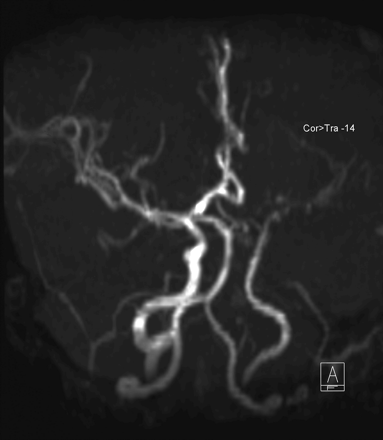

The left internal carotid artery (ICA) was very thin in caliber in all intracranial segments, tapered at the supraclinoid segment, and occluded at the bifurcation into the left middle and anterior cerebral artery (Fig 3). Thin basal collaterals in the left sylvian fissure and basal cisterns were observed on T2-weighted turbo spin-echo (TSE) imaging (Fig 2B).

Time-of-flight MR angiogram (TR/TE; 39/3.26) shows thin-caliber left ICA in all intracranial segments, with a tapering end and occlusion of the artery at its bifurcation.